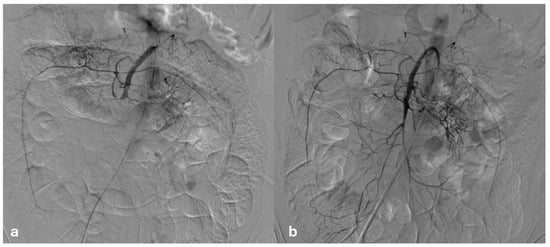

2. Case Report